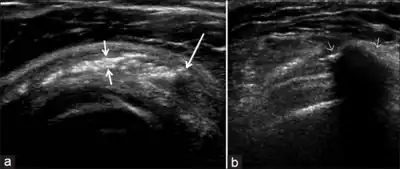

ULtrasound of calcific bursitis